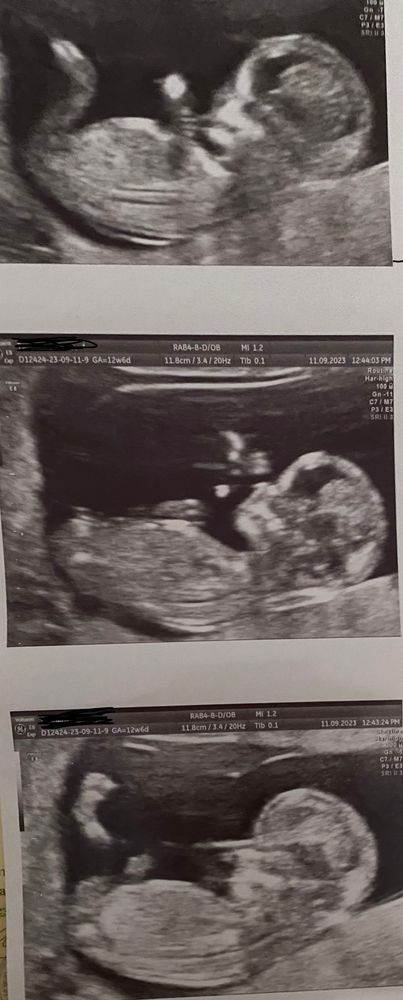

Если кто-то понимает в этом или может подобные фото узи были,на кого похож малыш ,мальчик или девочка?на фото срок 12,6 недель,до следующего узи две недели,я уже извелась догадками🤦♀️

Мне кажется это девочка, уж очень красивая))))).😀